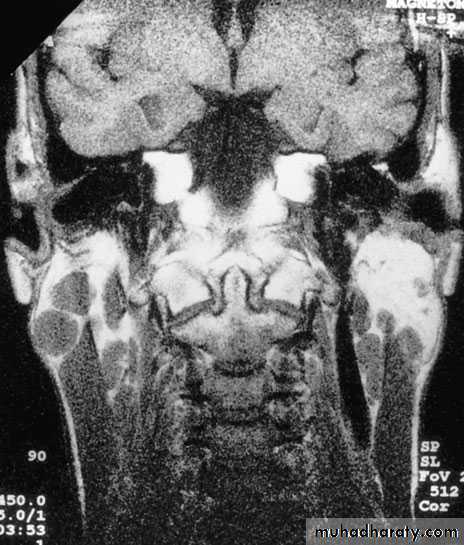

Diagnosis by CT,MRI (swiss-cheese of large cysts).

Magnetic resonance imaging (MRI) scan revealing aspace-occupying lesion (arrow) in the right parotid gland; histologyrevealed pleomorphic adenoma.Malignant salivary gland tumours are divided into two distinct sub-groups: